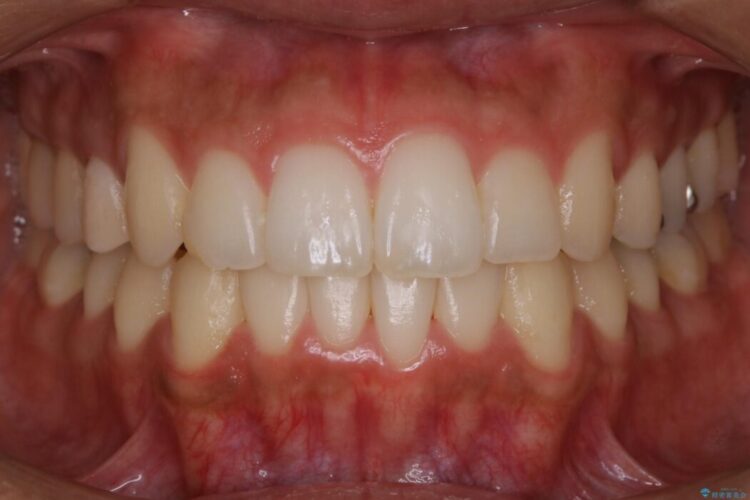

歯列のガタガタと飛び出ている前歯を治したいとのことで来院されました。

目立たない矯正装置をご希望でしたのでマウスピース装置(インビザライン)をご提案しました。

それにより従来の矯正治療と比べましても効率的に歯の移動を行えるため、非抜歯の場合でも歯列を整えることが可能となります。